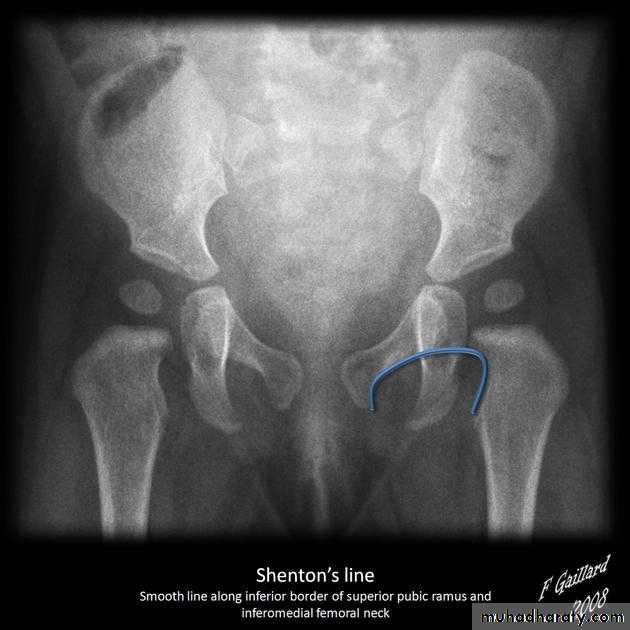

Who can you do Von Rosen view

At 3-6 months :abduction of the thigh 45 degree and internal rotation

Shenton line is drawn along the inferior border of the superior pubic ramus and should continue laterally along the infero medial aspect of the proximal femur as a smooth line. If there is supero lateral migration of the proximal femur due to DDH then this line will be discontinuousPerkin line is drawn intersecting the lateral most aspect of the acetabuler roof & iliac creast

Q…CDH occurs most commonly in ????(70%) in the left hip . Bilateral involvement is seen in 5%

Q…By simple diagram draw pelvis with lines (shenton’s & Perkins line)